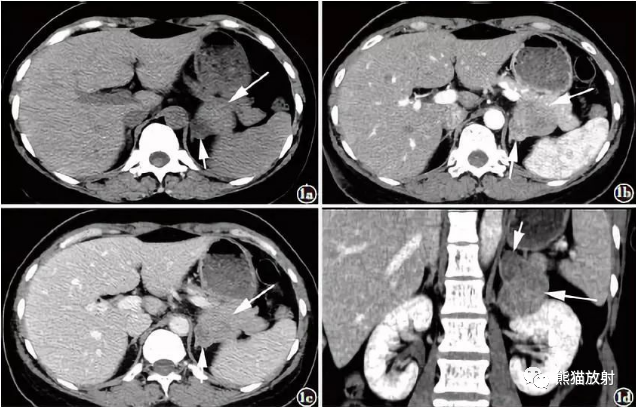

碰撞瘤(collision tumor):为同解剖位置形成的同一瘤块内,两种成分独立存在,紧密并列,分界清晰,在交界处两种不同的病理成分没有混合,两种成分组织发生,应为独立起源,且为原发性肿瘤。肾上腺碰撞瘤常见的来源有肾上腺皮质腺瘤与转移瘤或肾上腺间质来源的肿瘤。

腺瘤与嗜铬细胞瘤分别有独立完整的包膜,CT平扫分界清晰,均有各自的强化特点。肾上腺皮质腺瘤为肾上腺最常见的良性肿瘤,70%的腺瘤为富脂型,平扫CT值较低。化学位移MRI检测到细胞内脂肪的存在有助于腺瘤诊断,以此与嗜铬细胞瘤鉴别。88%的嗜铬细胞瘤有囊变,肿瘤体积越大,越易出现坏死及囊性变或出血,表现为T1WI及T2WI信号不均匀,大部分表现为实性部分明显不均质强化。

如发现CT或MRI表现明显不一样,包括肿块大小、平扫密度/信号、强化方式和强度等,结合临床内分泌结果,用一种肿瘤不能解释临床表现的时候,要怀疑两种不同肿瘤同时存在,要意识到碰撞瘤存在的可能性。